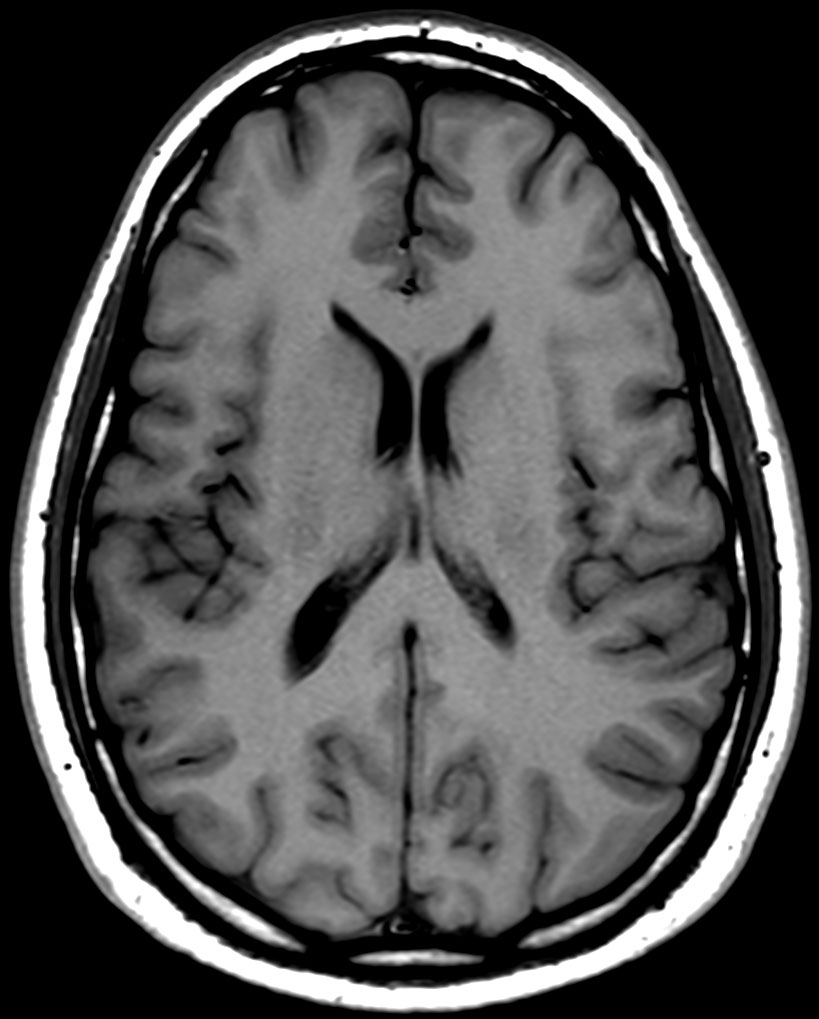

Brain imaging using ComforTone